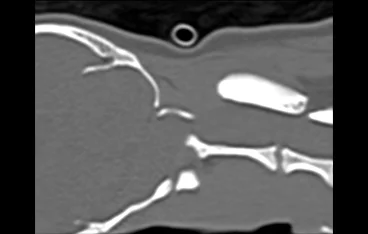

• 경추 디스크 MRI

• 경추 디스크